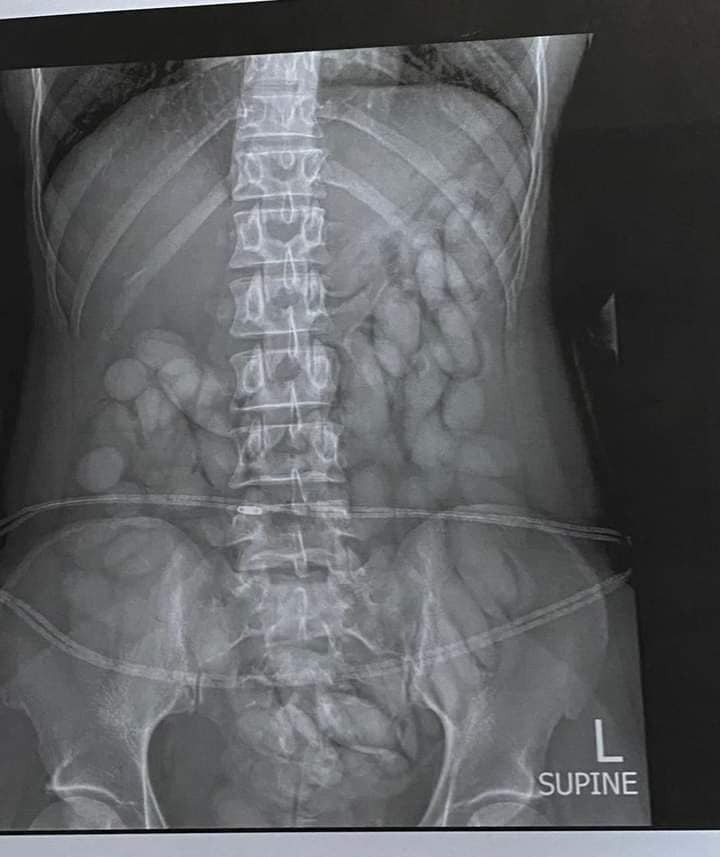

Mbangula was arrested at OR Tambo International Airport after arriving from São Paulo, where she had ingested over 68 cocaine pellets.